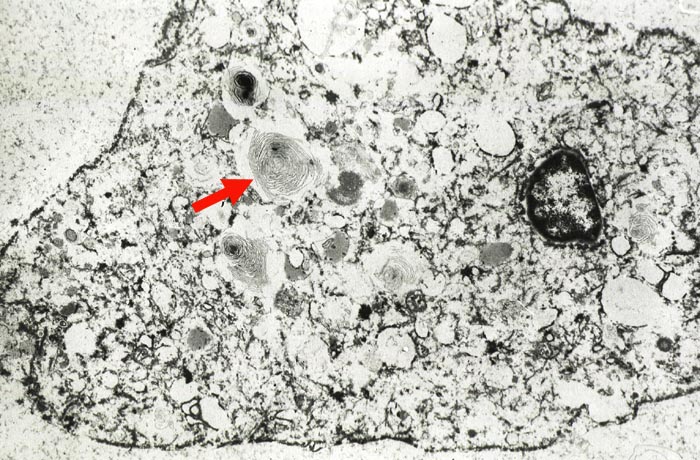

PathoPic ID 867 - Myelinartige Einschlüsse in Pneumozyten II nach Amiodarone

Myelinartige Einschlüsse in Pneumozyten II nach Amiodarone

Im Zytoplasma des Pneumozyten zahlreiche konzentrisch geschichtete an Myelin erinnernde

►

Einschlüsse.

7000x

Cordaronetherapie (Amiodarone)

Die Myelinkörperchen beweisen, dass der Patient Amiodarone eingenommen hat.